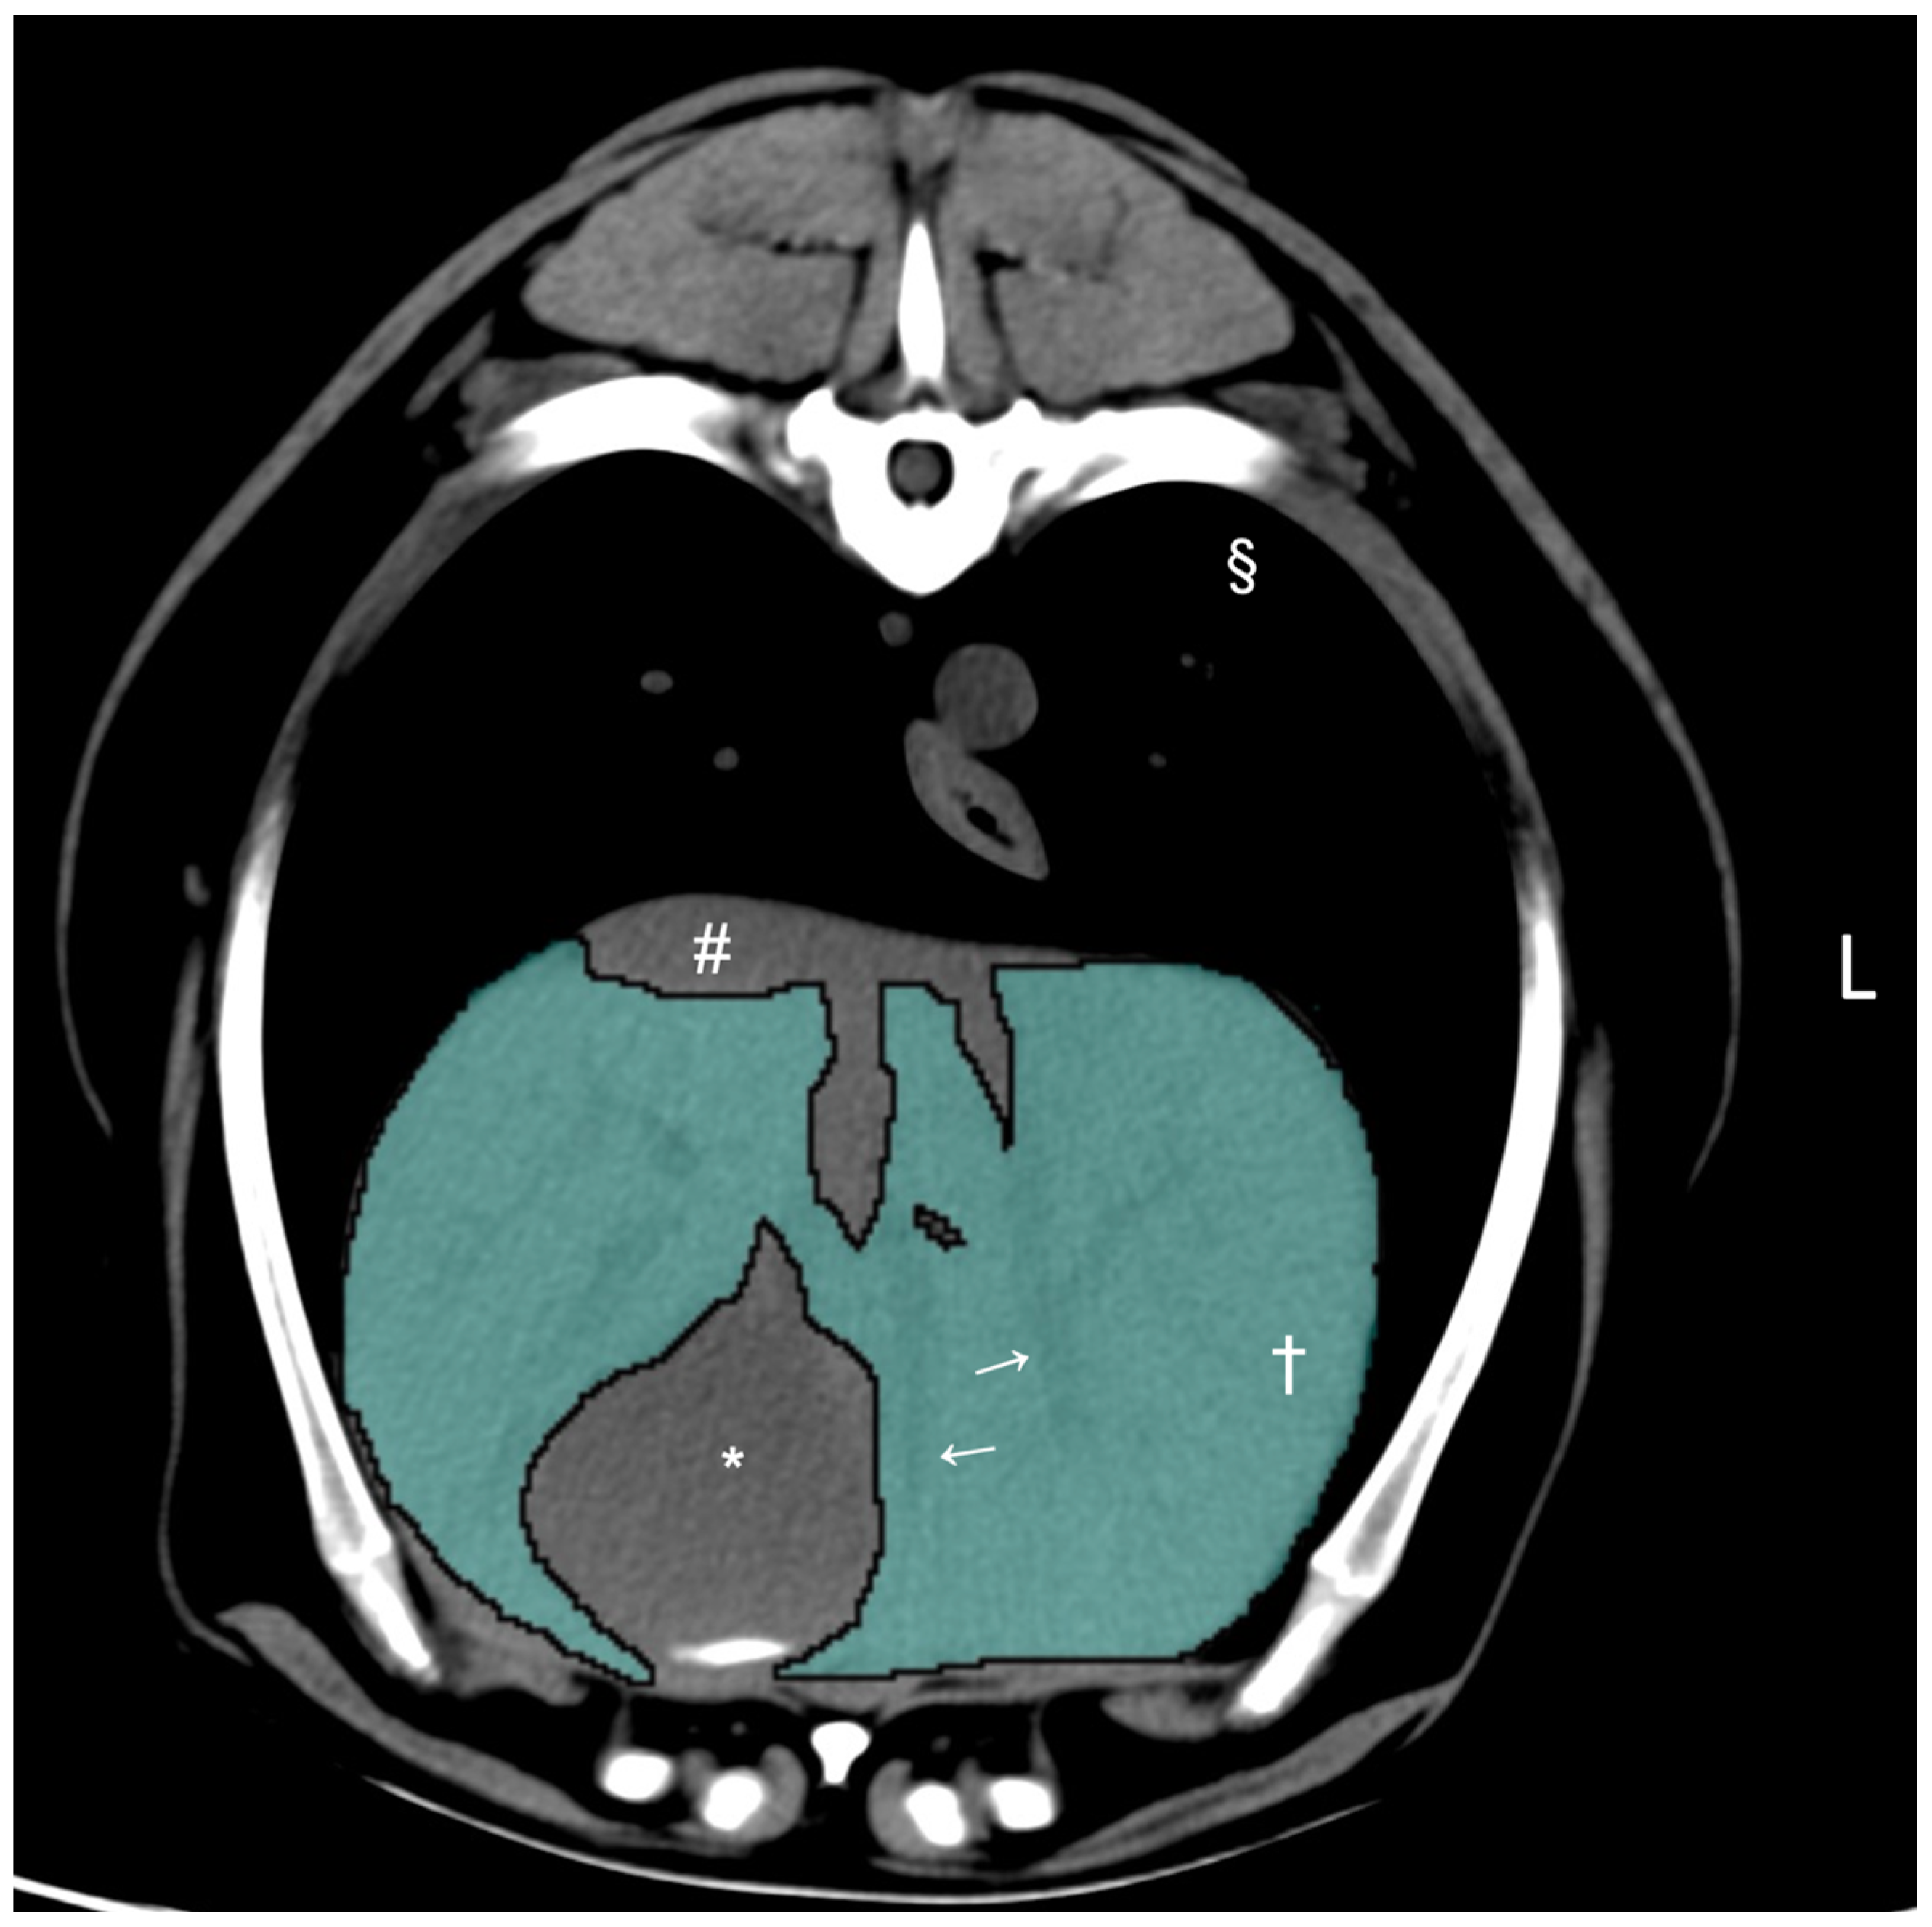

CT hepatic volumetry was performed by a veterinarian (K.K.) who had received training supervised by a board-certified radiologist (M.M.) using DICOM viewer (Horos 64-bit, version 3.3.6., Purview, Annapolis, MD, USA) according to a previously published method [16]. The window width was set at 350 HU and the window level at 40 HU for all dogs. The liver segmentation was performed by manually drawing the operator-defined region of interest (ROI) on pre-contrast transverse images of the entire liver, from the cranial margin of the liver at the diaphragm to the most caudal margins of the liver adjacent to the right kidney and the spleen. The ROIs included the hepatic vessels within liver parenchyma but excluded the gallbladder and visible hepatic lobe fissures and hepatic vessels that were present outside of the hepatic parenchymal margin (Figure 1). After manual drawing of the ROIs on the hepatic parenchyma with more than 20 slices, the CT-derived liver volume was computed using the following formula to estimate the liver volume: Σ {each slice area (cm2) × slice thickness (cm)} × total number of slices of hepatic parenchyma/number of slices [16].

Figure 1.

Pre-contrast transverse abdominal CT images used for CT hepatic volumetry in dogs. The segmentation of the liver was manually selected as the region of interest (ROIs: highlighted in blue). Note that the hepatic vessels within the liver parenchyma were included (white arrows). The gallbladder, hepatic lobe fissure, and hepatic vessels present outside the hepatic parenchyma were excluded. Window width, 350 HU, window level, 40 HU. Liver parenchyma (†), gallbladder (*), caudal vena cava (#), and pulmonary parenchyma (§).